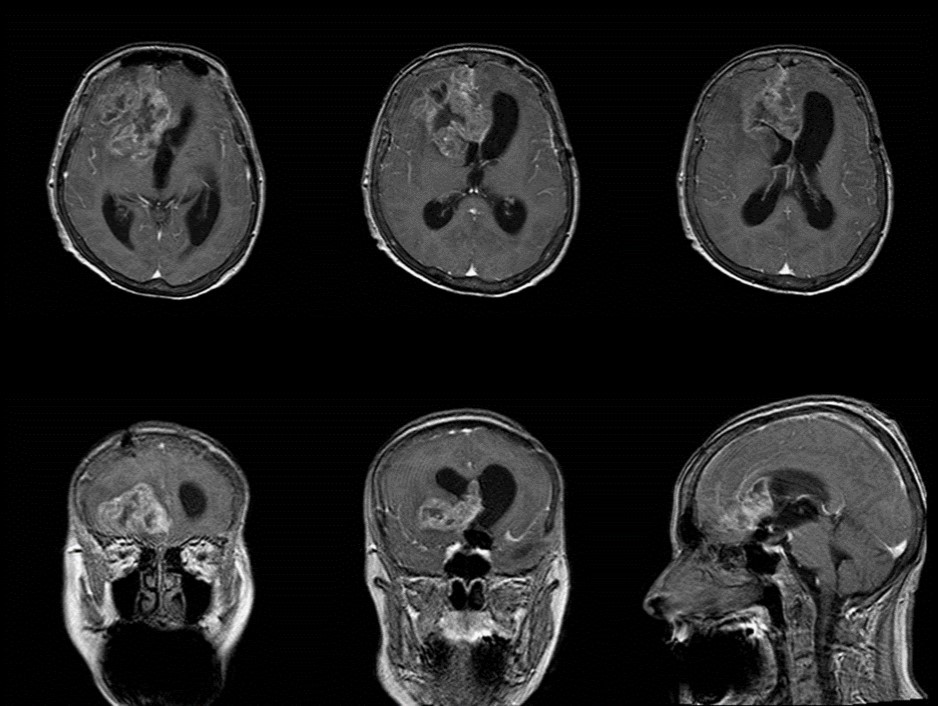

The follow-up CT scan made two weeks later showed a mild ventricular enlargement and persistent density alterations in the frontal region (Figure 2) that were interpreted as normal. Once discharged at home, the patient developed progressive disorientation that finally let her refer to our hospital for consult four months after aneurysm clipping. The cerebral CT we performed showed further ventricular growth, and a tumor-like image in the right frontal lobe (Figure 3). She was admitted to our ward and underwent a contrast-MRI that confirmed the suspicion of aggressive intra-axial neoplasm (Figure 4). The week after, under general anesthesia we performed a right craniotomy and removed a large part of the tumor, sparing the portion going through the corpus callosum (Figure 5). During convalescence the patient had few epileptic attacks, treated with drugs. A mild cognitive impairment persisted after surgery, without focal motor deficits. The gait, limited and unstable since the SAH, remained poor and the patient never walked again after the operation. The histological examination indicated a WHO grade IV glioma: IDH1-p53 negative glioblastoma. The patient and her relatives refused a ventriculo-peritoneal shunt after knowing this unfortunate diagnosis. Transferred to rehabilitation, the woman made just a short low-dose chemotherapy cycle and finally died four months after tumor resection.

Figure 4.Pre-operative contrast axial, coronal and sagittal MRI. Glioma of the right frontal lobe, extending contralaterally